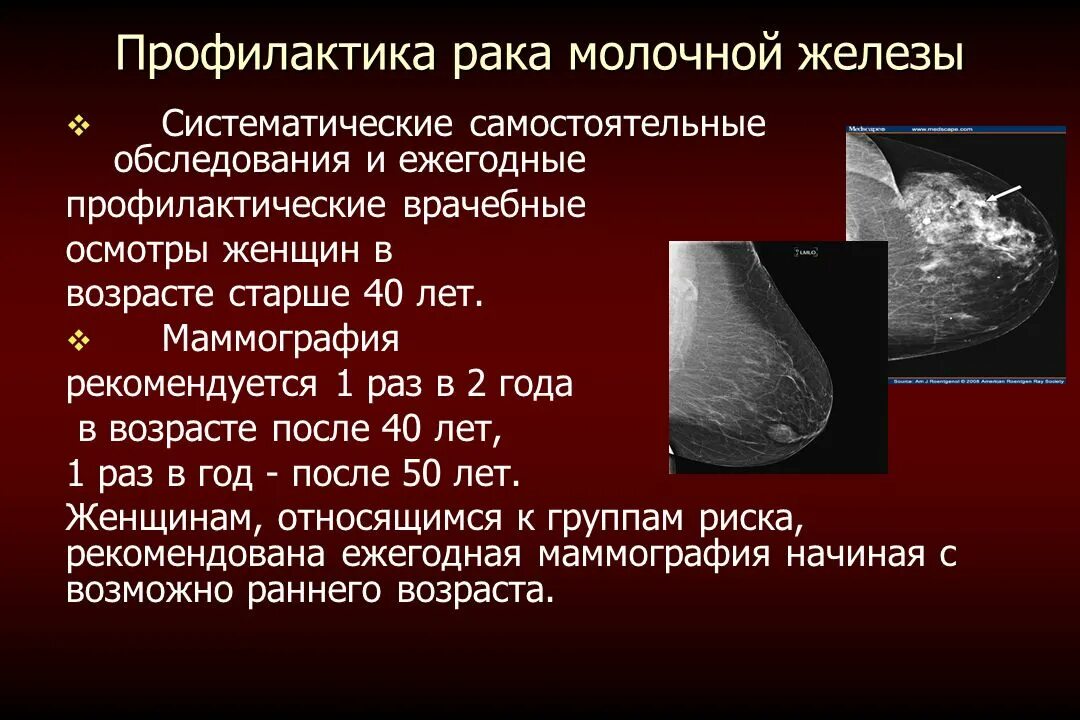

Петрокливальная менингиома. Менингиома доброкачественная. Злокачественные заболевания молочных желез. Новообразование молочной железы. Злокачественная опухоль молочной железы. Доброкачественные новообразования молочной железы.

Злокачественные заболевания молочных желез. Новообразование молочной железы. Злокачественная опухоль молочной железы. Доброкачественные новообразования молочной железы. Очаговые симптомы опухоли затылочной доли. Клинические проявления опухоли лобной доли:. Опухоль мозга височной доли симптомы. Опухоль затылочной доли головного мозга.

Гепатомегалия. Симптомы гепатомегалии. Умеренное увеличение печени. Умеренная гепатомегалия. Маммография косая проекция укладка. Маммография молочных желез. Маммография это исследование. Рентгеновская маммография.

Маммография косая проекция укладка. Маммография молочных желез. Маммография это исследование. Рентгеновская маммография. Подчелюстная слюнная железа на рентгене. Сиалография слюнных желез. Рентгенография слюнных желез. Контрастная сиалография слюнных желез.